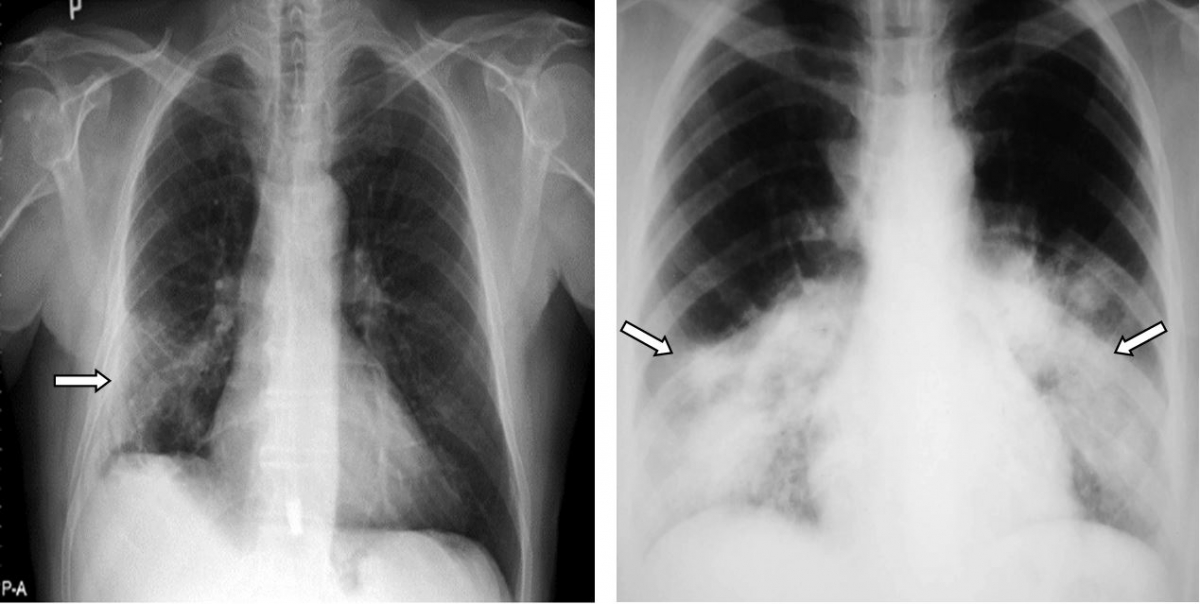

Tình trạng xơ hóa này có thể được nhìn thấy trên mô bệnh học qua sinh thiết phổi hoặc hình ảnh xơ trên phim CT scan. Đi kèm với nó là tình trạng giảm thể tích phổi và giảm độ khuếch tán của phổi qua các thăm dò chức năng hô hấp.

Tỉ lệ bệnh nhân có hình ảnh xơ hóa (giai đoạn sớm) trên CT scan khoảng 70-80% bệnh nhân viêm phổi trung bình và 100% bệnh nhân ARDS ở tại thời điểm xuất viện (khoảng 4 tuần sau khởi phát).

Nhưng tình trạng trên sẽ giảm dần theo thời gian. Sau 3 tháng, hình ảnh tổn thương xơ trên CT scan còn khoảng 50% bệnh nhân viêm phổi trung bình và 70% bệnh nhân nặng. Sau 6 tháng, tỉ lệ này là khoảng 30%.

Trên phim chụp CT scan ngực, hình ảnh xơ hóa phổi biểu hiện dưới nhiều dạng và mức độ như: hình ảnh dải xơ, dày các vách liên tiểu thùy, hình ảnh lưới, dãn phế quản co kéo và điển hình nhất là hình ảnh tổ ong